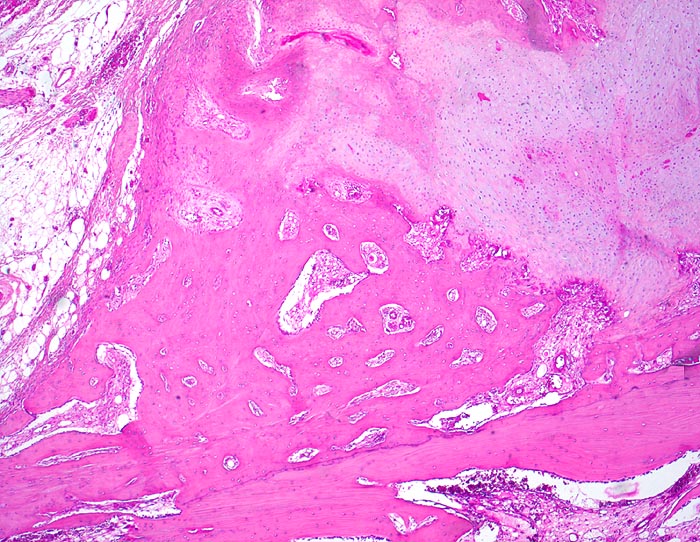

sekundäre Frakturheilung: Kallus

Knochen, Rippe

Dem Frakturspalt aussen aufsitzender knöcherner und knorpliger Kallus mit Zonen der enchondralen Ossifikation. Extraperiostales Fettbindegewebe.

Konservativ behandelte Rippenfraktur nach Sturz vor einem Monat.

Die Frakturenden werden durch den Kallus überbrückt. In der Frühphase der Heilung wird ein Übermass an Bindegewebe, Knorpel und Knochen gebildet vor allem bei ungenügender Ruhigstellung. Während der Ausreifung des Kallus werden diejenigen Gewebsanteile, welche keiner erhöhten Belastung ausgesetz sind, wieder resorbiert. Der Kallus wird im Verlauf der Zeit zunehmend kleiner.

25